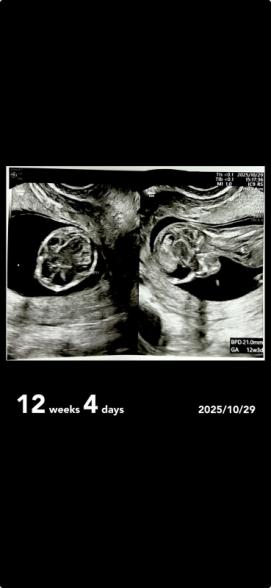

頭の脳みそは12週目だったらみんなこんな感じなんですかね?

他の人のエコーとか見ていたら少し違う気がして気になりました。(一枚目)

首の後ろのむくみとかで分かるって書いていて、見てもわからなくて、背中の後ろの線はなんなのでしょうか

これは浮腫なんですか??

首の後ろの線は、空洞の部分が大きく、首の浮腫とは考えにくいかなと思います。卵膜など赤ちゃんが包まれている膜かなと思いますが、はっきりとは断言できないので医師に確認してみてください。

答えられる範囲ですと、超音波検査でダウン症の診断はできないかと思います。そのほかの染色体異常も特徴的な所見があれば、もっと細かい超音波検査をすることになるかと思います。何かあれば必ず医師は説明してくれると思いますので、今回特に何も説明がなければ、今のところは問題ないと思っていただいて良いかなと思います。次回の健診でも、相談してみてくださいね。